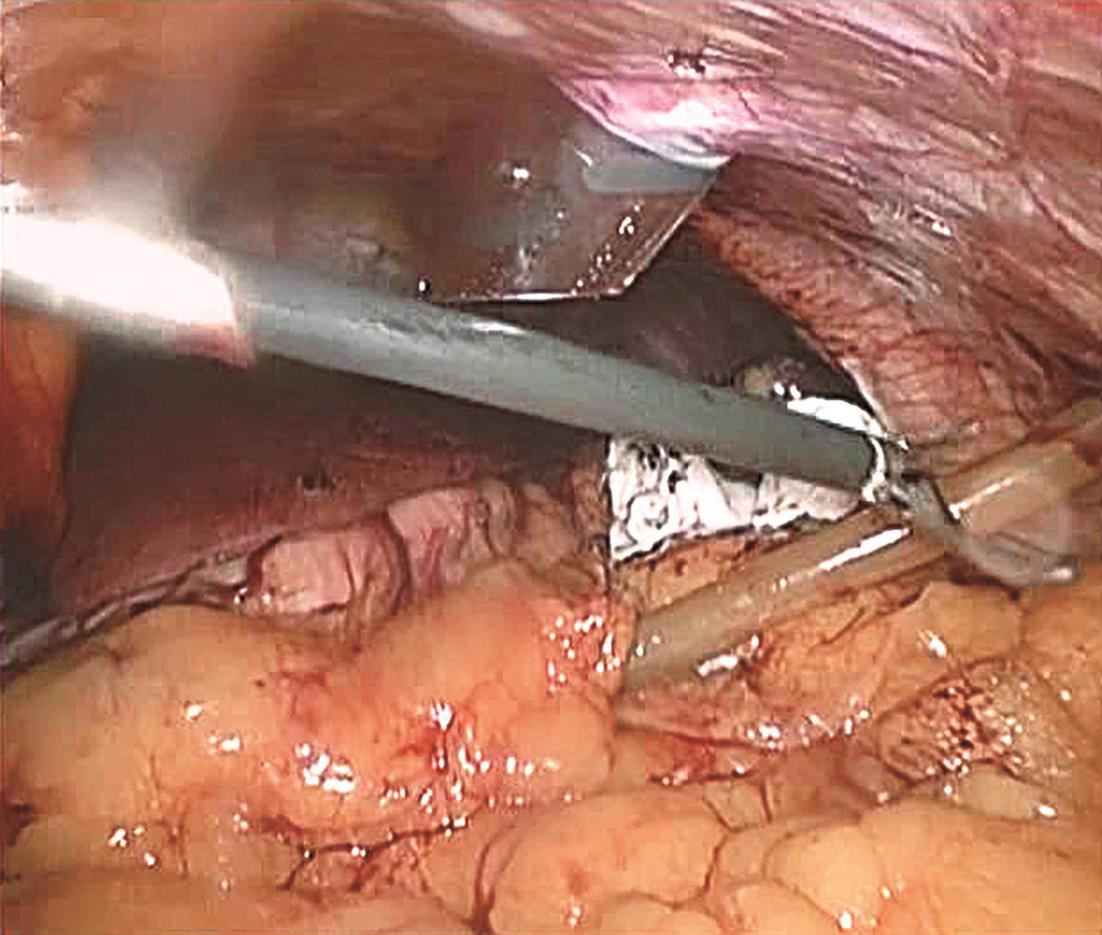

患者取平卧位,头高脚低,四孔或三孔法操作;首先自胃网膜血管弓下方横行打开胃结肠韧带(图6-1),探查胰腺颈、体、尾,必要时可打开胰腺下缘被膜,游离胰腺后方深入探查;清楚定位肿瘤后,镜下缝合肿瘤一针作为牵引用(图6-2),超声刀紧贴肿瘤,完整剜除;检查胰腺创面,选择性缝合创面(图6-3);取出标本,送冰冻,留置引流,关闭腹壁切口,术毕(图6-4)。

图6-4 创面留置引流管一根